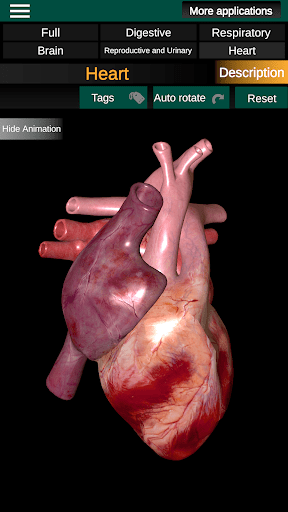

* Серце, що включає передсердя, шлуночки, аорту і одушевлення цього органу.

* Легкий доступ і навігація (масштабування, 3D-обертання).

* Описи кожного органу.